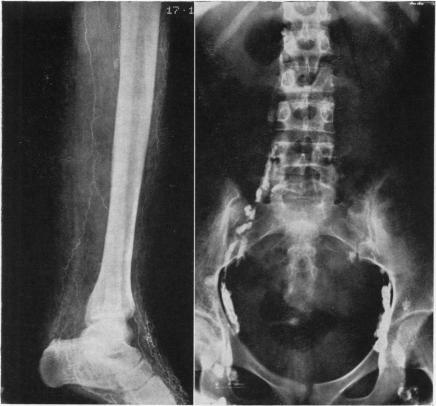

LYMPHANGIOGRAPHY AND CHROMOSOME STUDIES IN FEMALES WITH LYMPHOEDEMA AND POSSIBLE OVARIAN DYSGENESIS.

Arch Dis Child. 1965 Feb;40(209):27-32. doi: 10.1136/adc.40.209.27.